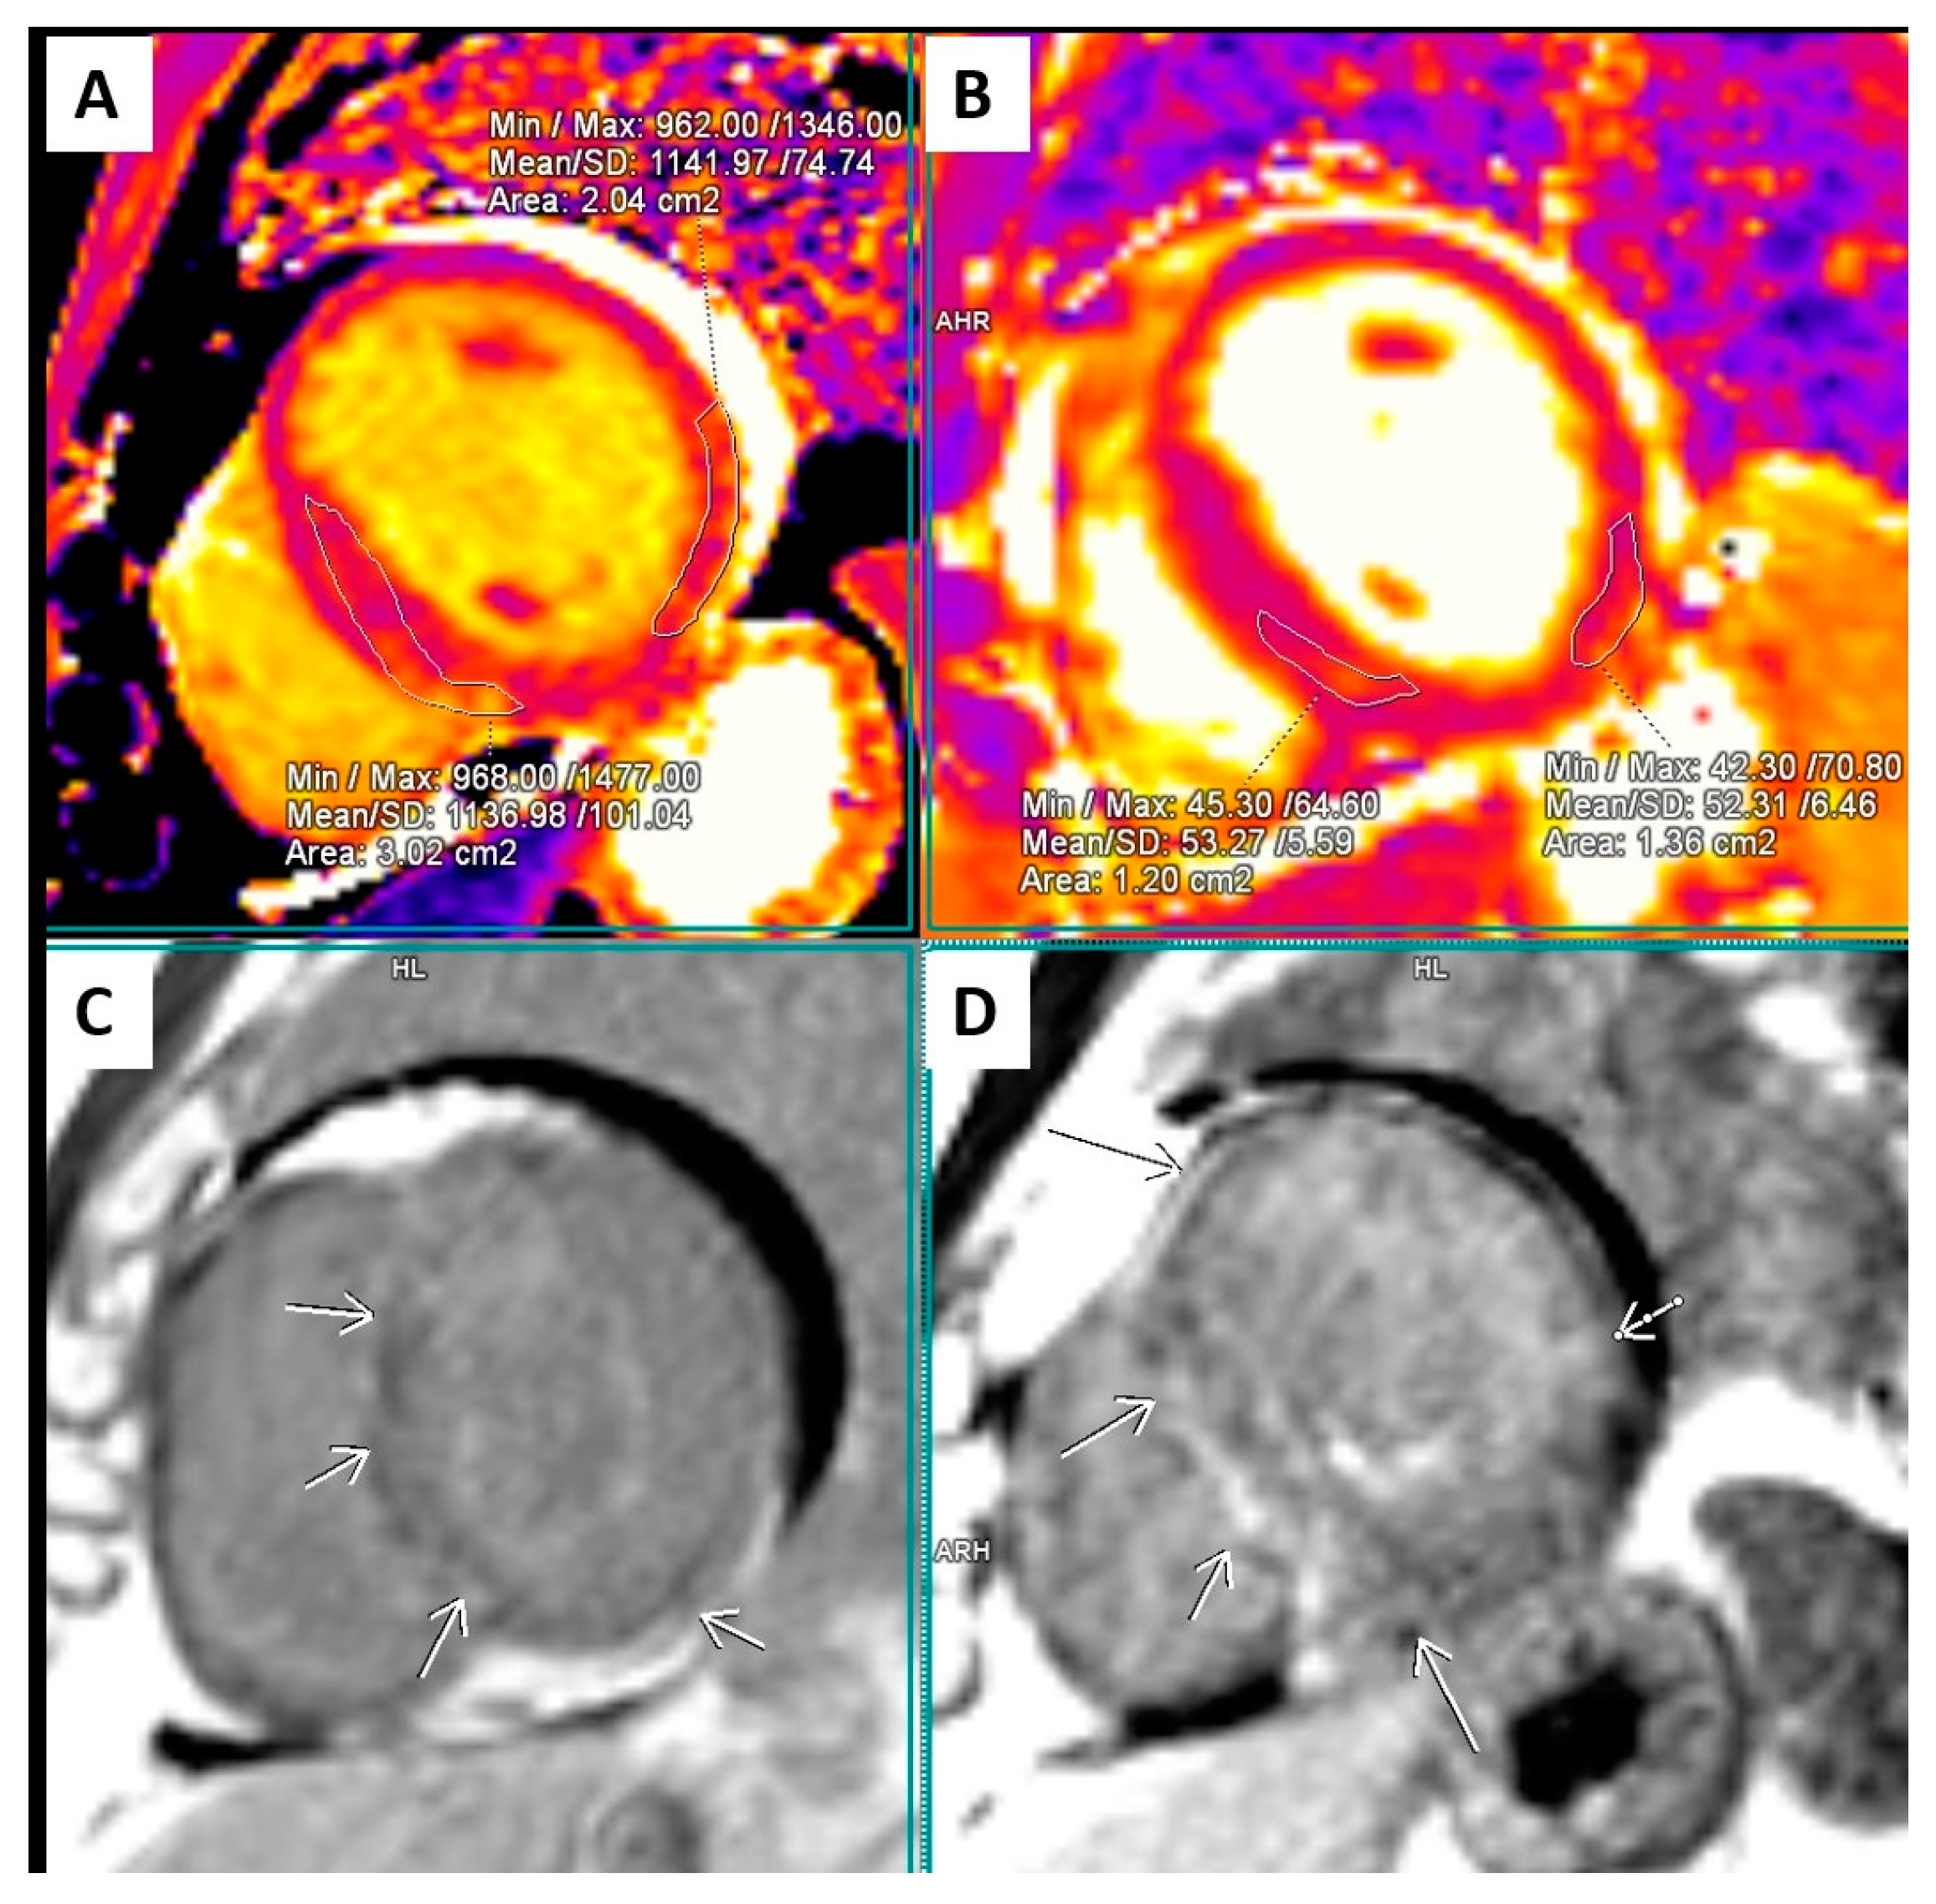

2.2. Cardiac Magnetic Resonance (CMR)

| March 2021, age 45 | First episode of decompensated heart failure, NYHA III-IV class; A new episode of persistent AF, duration longer than two months | Management of failure according to guidelines; TEE not performed due to INR not being in target; Asymmetric left ventricular hypertrophy and reduced ejection fraction noted; Further diagnostic work-up recommended—cardiac magnetic resonance (CMR) and genetic testing; Test for Anderson–Fabry disease—negative; CMR study positive for cardiomyopathy with diffuse fibrosis, possibly hypertrophic or infiltrative. | At admission: Amiodarone 400 mg; Torasemide 20 mg; Irbesartan 75 mg; Acenocoumarol; At discharge: Torasemide 50 mg; Spironolactone 50 mg; Acenocoumarol; Bisoprolol 5 mg; Sacubitril/valsartan 2 × 24/26 mg; Allopurinol 150 mg; Dapagliflozin 10 mg |